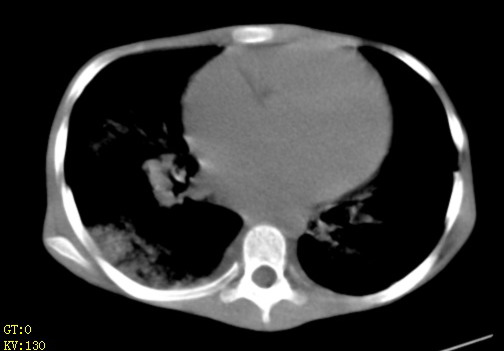

女,12岁,气促、咳嗽2天,3个月前查胸片示:两肺感染,急诊入院查ct,血常规等未检查。

先心(室缺?)、左室大,心功能不全;肺部感染

1、左心房、左心室增大,考虑左心衰, 2、肺水肿合并感染 3、双侧胸腔积液

双肺中下野不规则片絮状阴影,中外带明显,双侧胸腔少量积液,心影增大,心腔密度减低,隆突下及左侧气管旁见钙化淋巴结影,考虑双肺感染、心衰;建议结合临床除外h1n1并急性心衰,先心不能排除。